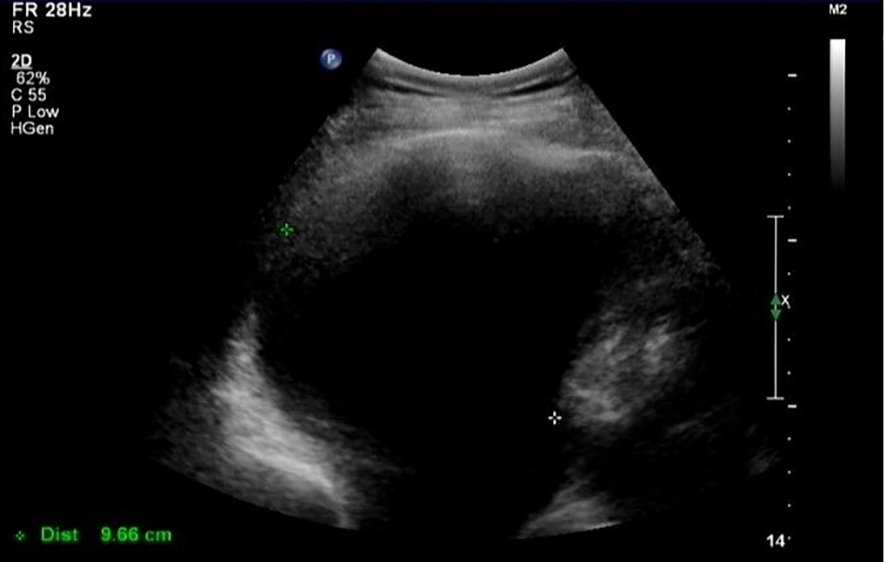

In March 2021 (3 months after the last chemotherapy), a hard mass that was approximately 5 cm in diameter on the left lower jaw was palpable. CA-125 was 1,863 U/mL. Ultrasound result showed a right pleural effusion (9.8 cm in depth, Figure 1). Thoracentesis was performed, and the drainage fluid had a milky white appearance (Figure 2). The laboratory analysis of the pleural fluid revealed exudative chylous fluid with triglyceride levels >1.24 mmol/L (110 mg/dL), a cholesterol level <5.18 mmol/L (200 mg/dL), and a positive chyle test. Cytological pathology revealed adenocarcinoma cells. The patient was diagnosed with platinum-resistant recurrence of ovarian cancer combined with right-sided chylothorax. Conservative treatment of chylothorax and chemotherapy for recurrent ovarian cancer were recommended by a multi-disciplinary team, including nutriology, respiratory oncology, thoracic surgery, and intervention departments. Surgery was not feasible because of disseminated multiple metastatic enlarged lymph nodes of ovarian cancer. Chylothorax was managed conservatively, including a strict diet with low-fat medium–long-chain triglycerides and chest tube insertion with interleukin-2 intrapleural perfusion (3 million units). Chylothorax improved significantly with progressively reduced and transparent pleural effusion (Figure 2). The drainage fluid was reduced to 50 mL/day on the fifth day, and then the drainage tube was removed. However, long-term intake of medium–long-chain triglycerides affected her quality of life negatively, and the patient was not able to adhere to the diet plan and gradually resumed the regular diet. Therefore, chylothorax recurred, and thoracentesis was performed repeatedly with IL-2 or cisplatinum pleural perfusion at intervals of 2–5 months (a total of six times). Chyle was produced slowly and did not affect the quality of life of the patient. Oral etoposide and bevacizumab were maintained from November 2021 to May 2022 (the patient refused PARP inhibitors due to economic reasons). The patient achieved a partial response (CA-125 91 U/L, lymph node reduction, and pleural fluid maintained at 3.1–5.8 cm).

Figure 1

Ultrasound image of pleural effusion.